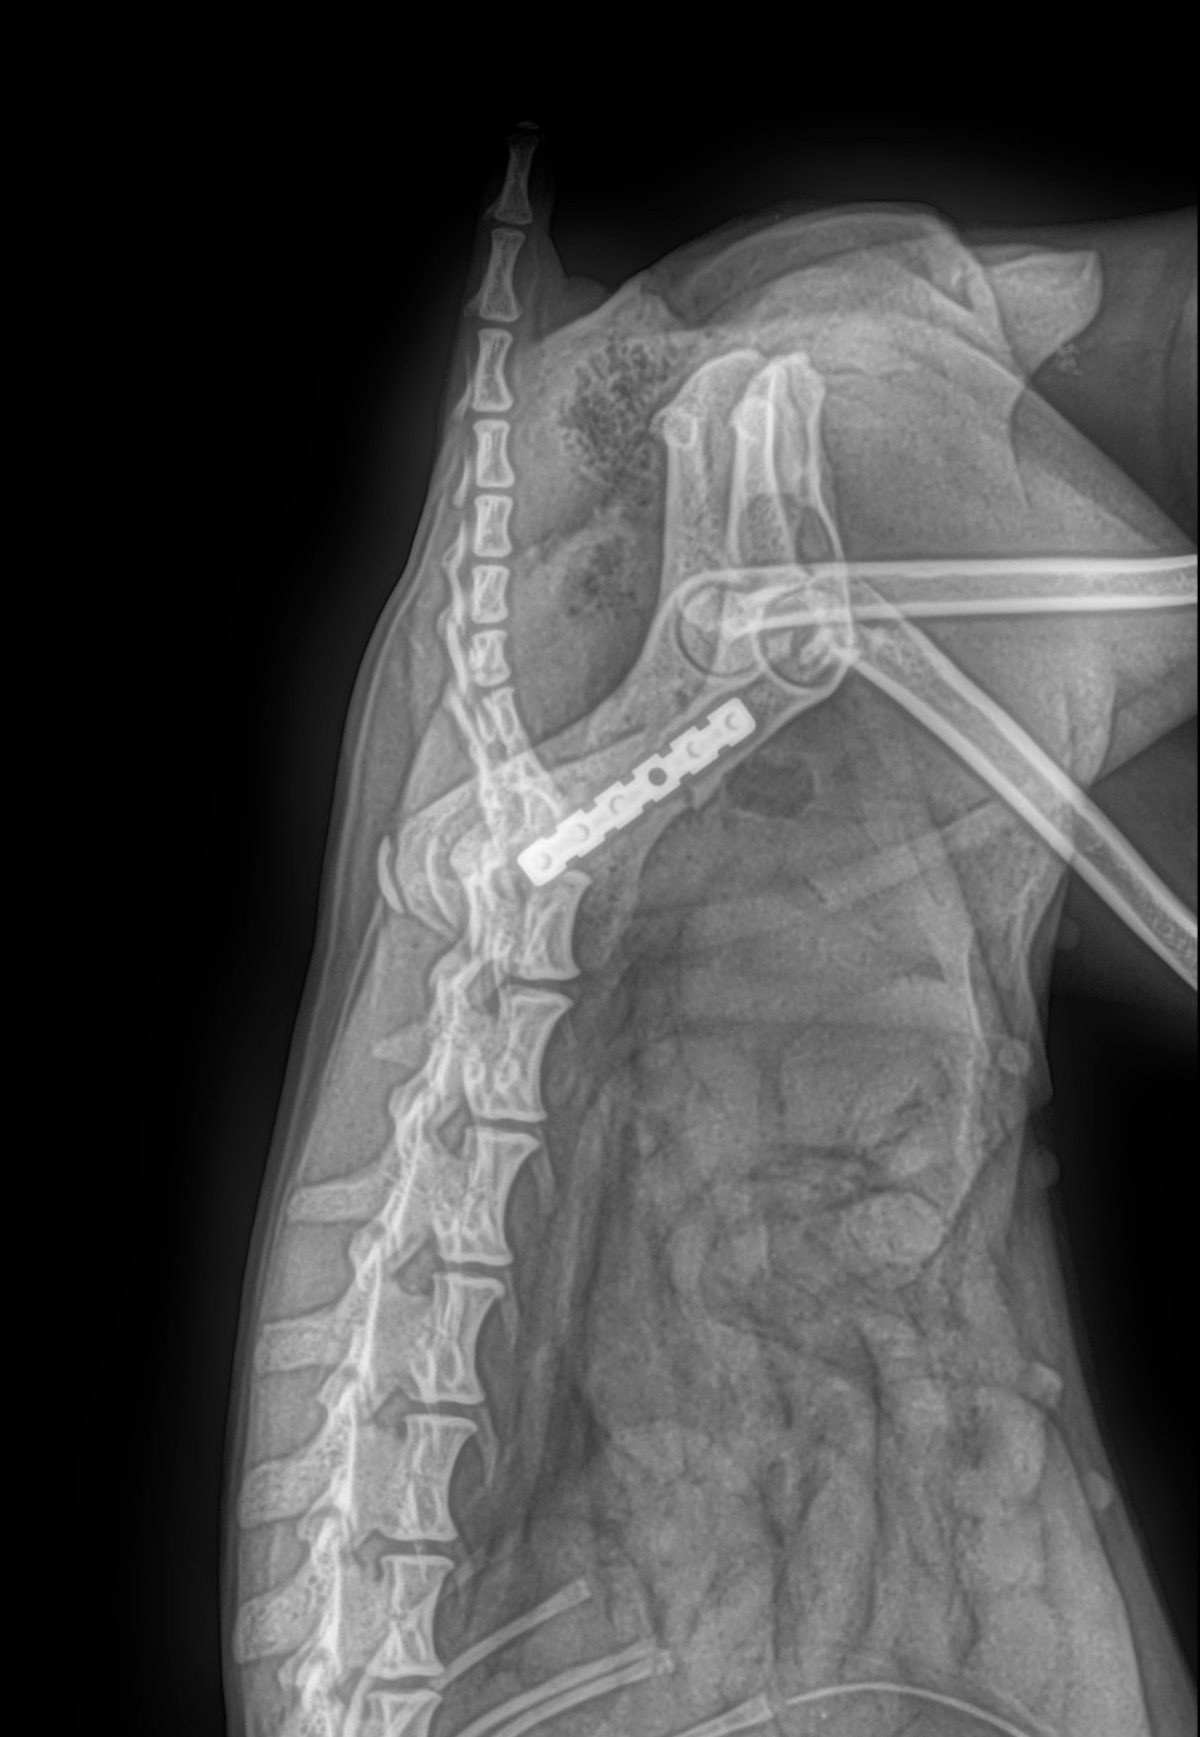

Radiología Digital como Herramienta Complementaria en el Dictamen de Bienes Muebles

Desde el descubrimiento de los rayos “X” y las placas radiográficas por Wilhelm Conrad Roentgen y su posterior difusión a través de la Asociación Físico médica de Wurzburg el 28 de diciembre de 1895, que fue la primera asociación que habló de los nuevos rayos que podían penetrar el cuerpo y fotografiar los huesos, ha habido muchos cambios tanto en la forma de obtener, procesar e incluso en la forma de visualizar, manejar y almacenar las placas radiográficas.